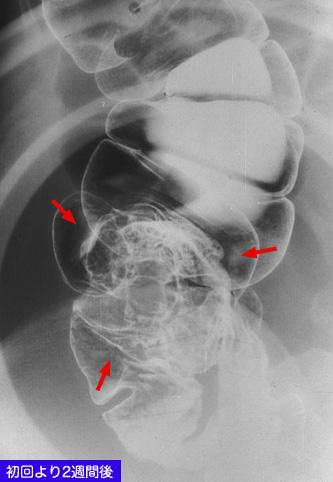

Cáncer Avanzado del Colon tipo I, hecho de la Intususcepción Intestinal contiguo al apéndice

[Image-ID:10358]

Tumor Epitelial Maligno/Adenocarcinoma

colon/ciego

Rayos X

Tipo 1(Tipo protuído)/

40 -

ss(a1)